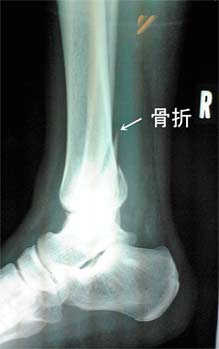

2007050203.jpg

この写真は足を外側に広げて取った物です。

これだと最初の写真の内側の部分が、ぽっきりと折れて外れているのが判ります。

2007050204.jpg

この写真は足の内側を下にして撮った物です。

これが筋肉を傷つけていたらもっと痛かったと思われます。